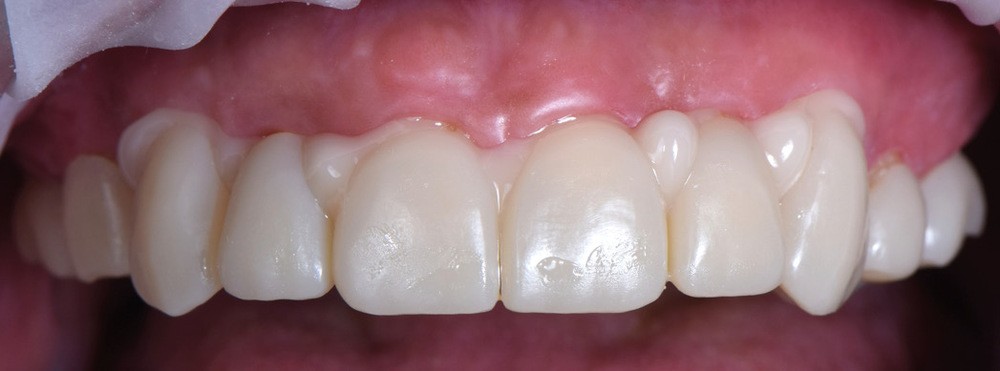

Au vu du contexte para-fonctionnel et de l’étendue de la perte tissulaire, des coiffes périphériques minimalement invasives ont été choisies afin de restaurer l’esthétique et la fonction. Actuellement, aucun consensus n’est fait sur le choix du matériau d’infrastructure à privilégier. Les matériaux hybrides usinables présentent des propriétés mécaniques, physiques et biologiques intéressantes en contexte d’usure sévère (e.g., module d’élasticité, résistance à la propagation de fêlures, facilité de réintervention). Une réhabilitation globale avec remontée de dimension verticale d’occlusion (DVO) par l’intermédiaire de coiffes composites renforcés en nano-céramiques est décrite.